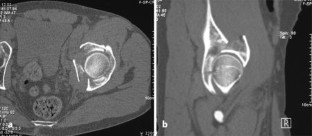

Vordere Pfeilerfraktur des Acetabulums mit dorsaler Impression

Anterior column fracture of the acetabulum with dorsal impression

Es wird ein ungewöhnlicher Fall einer vorderen Pfeilerfraktur des Acetabulums mit ausgedehnter Impression im Bereich des hinteren Pfeilers beschrieben. Nach primärer Osteosynthese über einen ilioinguinalen Zugang erfolgt die Reposition der dorsalen Impressionen über einen hinteren Zugang mit Repositionskontrolle mittels chirurgischer Hütluxation.

An unusual case of an anterior column fracture of the acetabulum with extended marginal impaction at the posterior column is presented. Fracture fixation was primarily performed by an ilioinguinal approach followed by a posterior approach with surgical dislocation of the hip to reduce the impacted fragments.